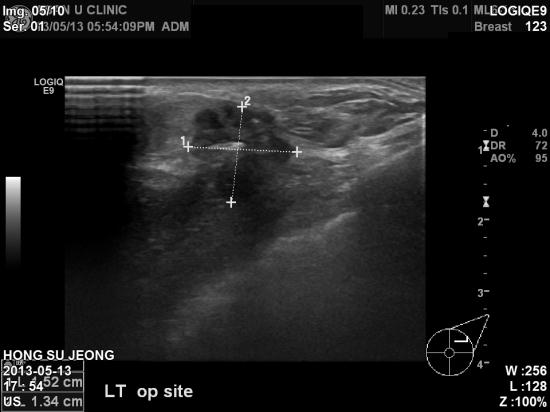

수술부위유두가 함몰된지 1년이 지나서야 검사해야 할 필요를 느끼셔서

본원에 조직검사

의뢰되셨습니다.

겨드랑이, 흉부내유, 쇄골부위 임파절등의 비대 의심 소견은 없어서 다행이나

유방의 바닥을 구성하는

가슴의 근육에 침범이 의심되는

침윤성 유방암 재발이 진단되었습니다.